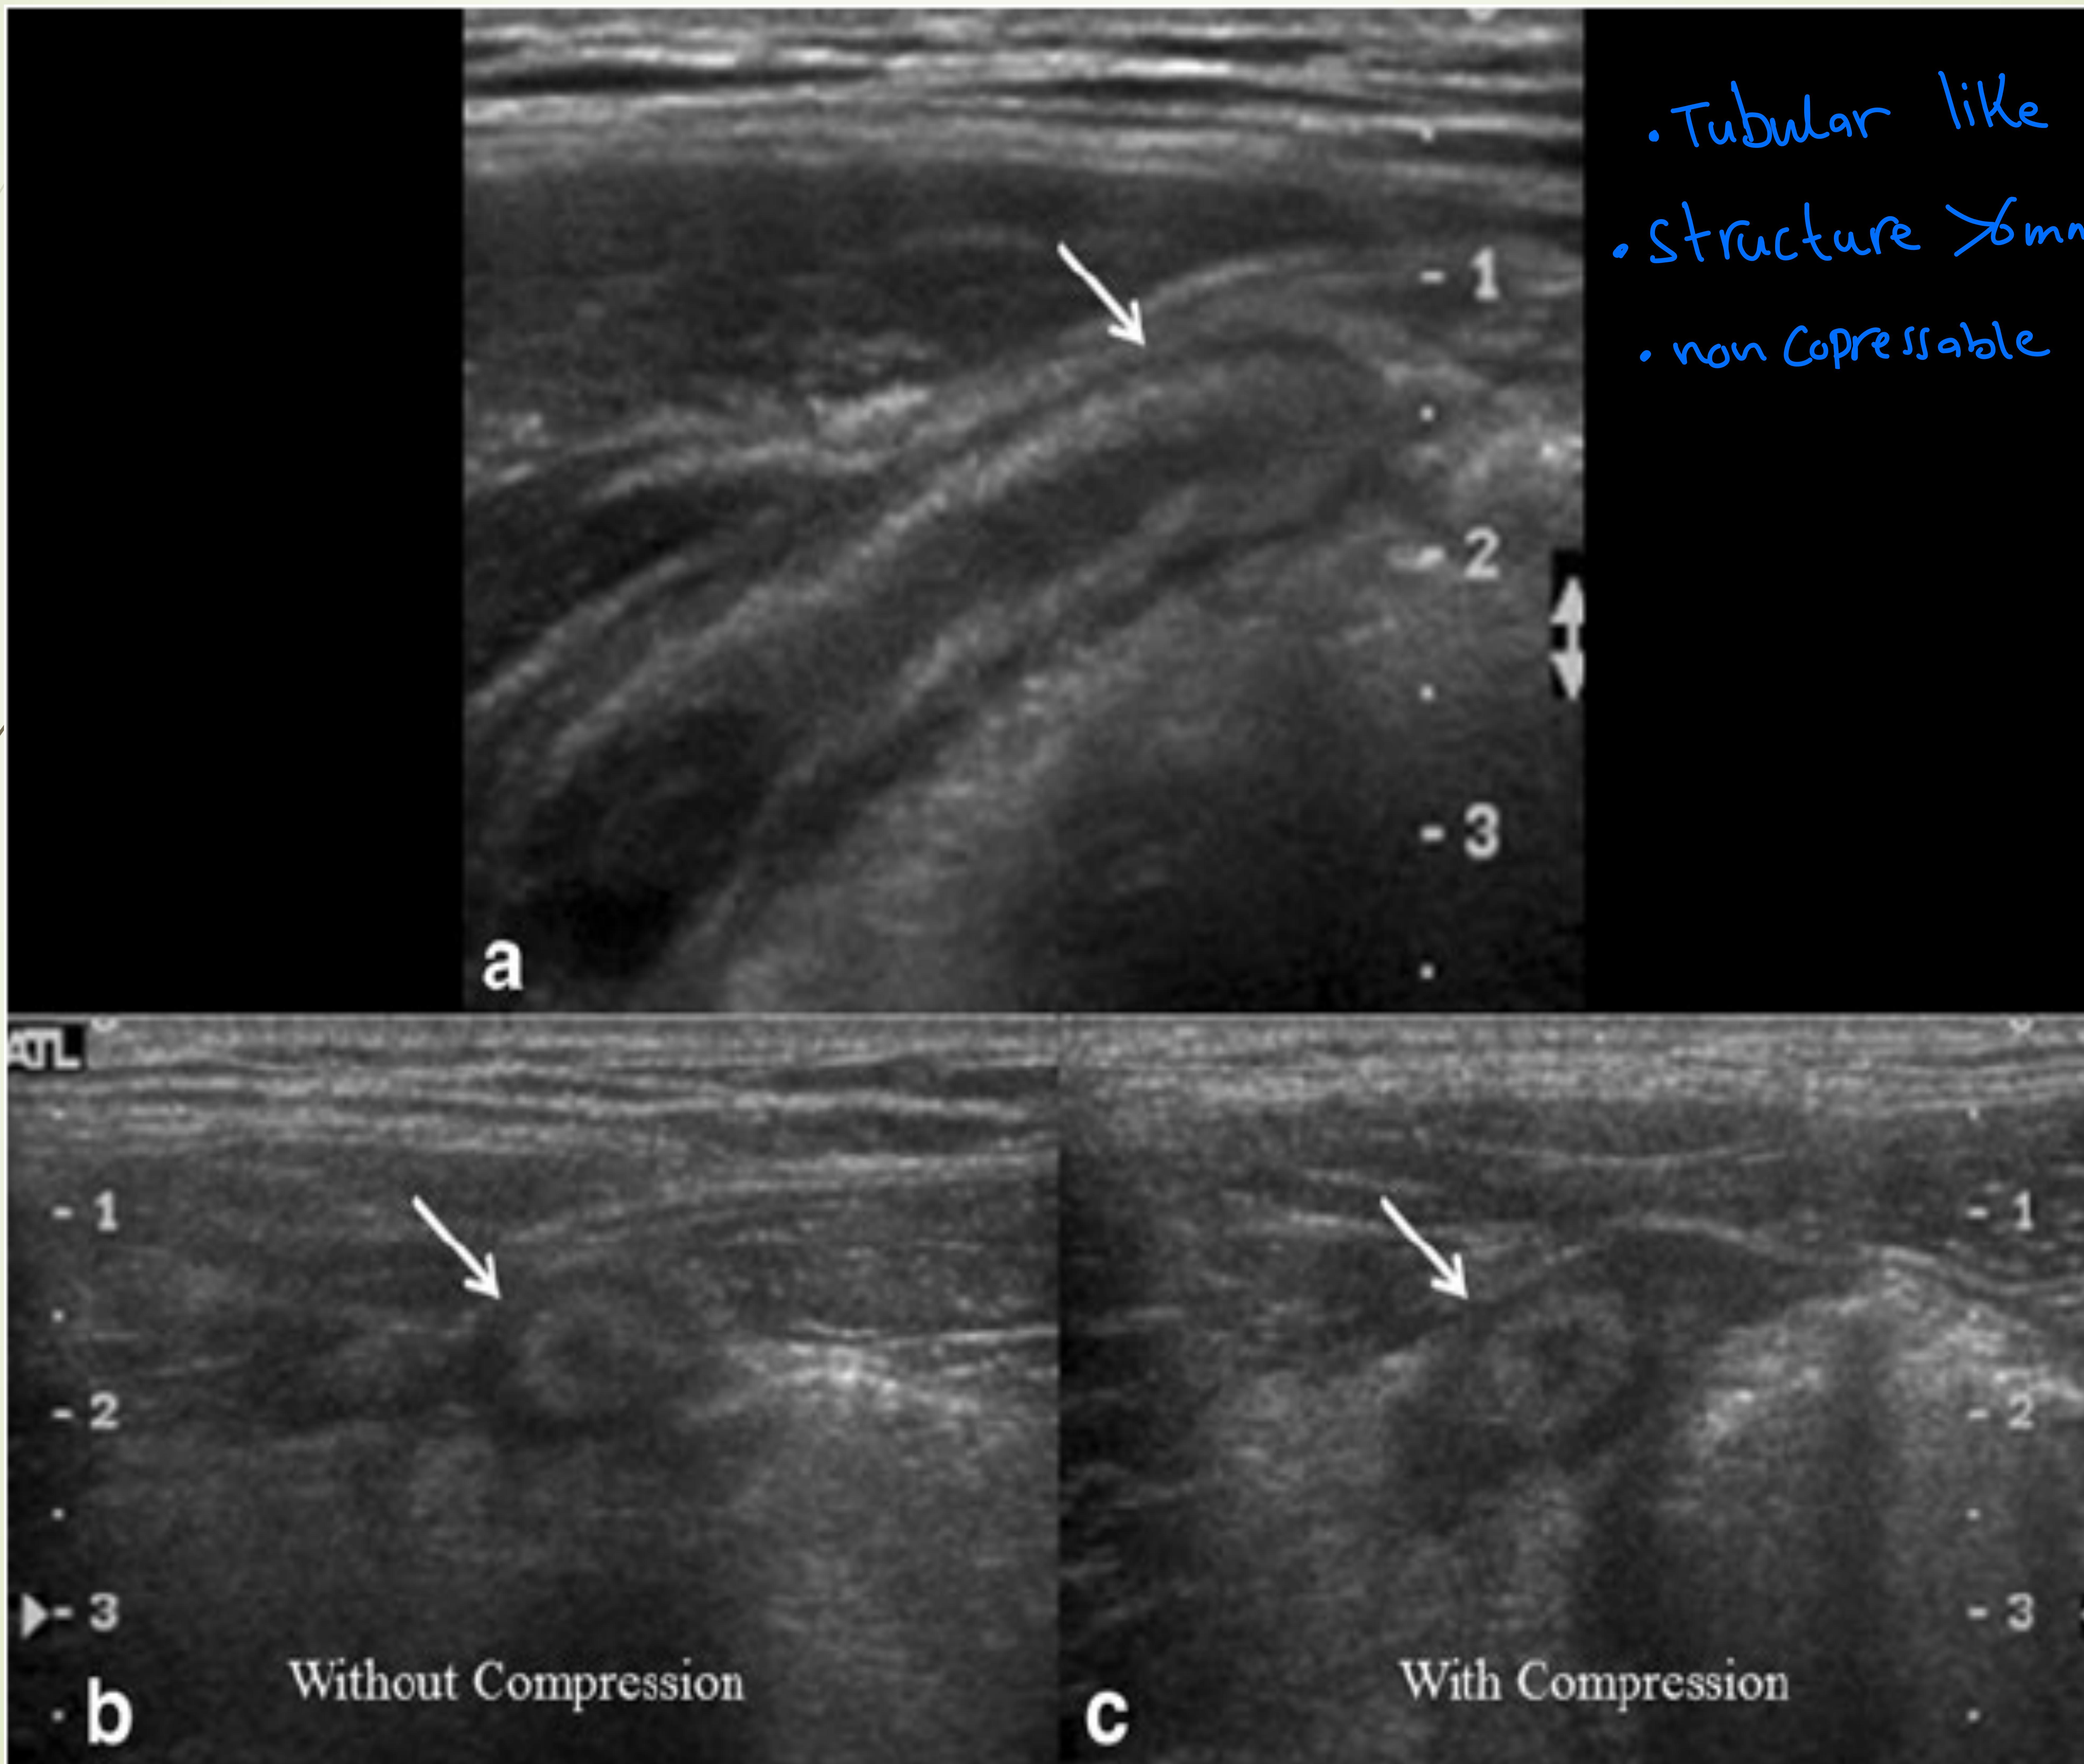

Ultrasound showing tubular structure >6mm, non-compressible.

- Diagnosis: CT Scan with contrast in male or nonpreganant women (Gold Standard) showing dilated appendix (>6mm), fat stranding. - otherwise use ultrasound

- Ultrasound: useful, operator-dependent (consider in children & pregnancy)

- CT scan (gold standard) — typical findings:

- Pericecal inflammation

- Abscess or localized fluid collection

- Localized fat stranding